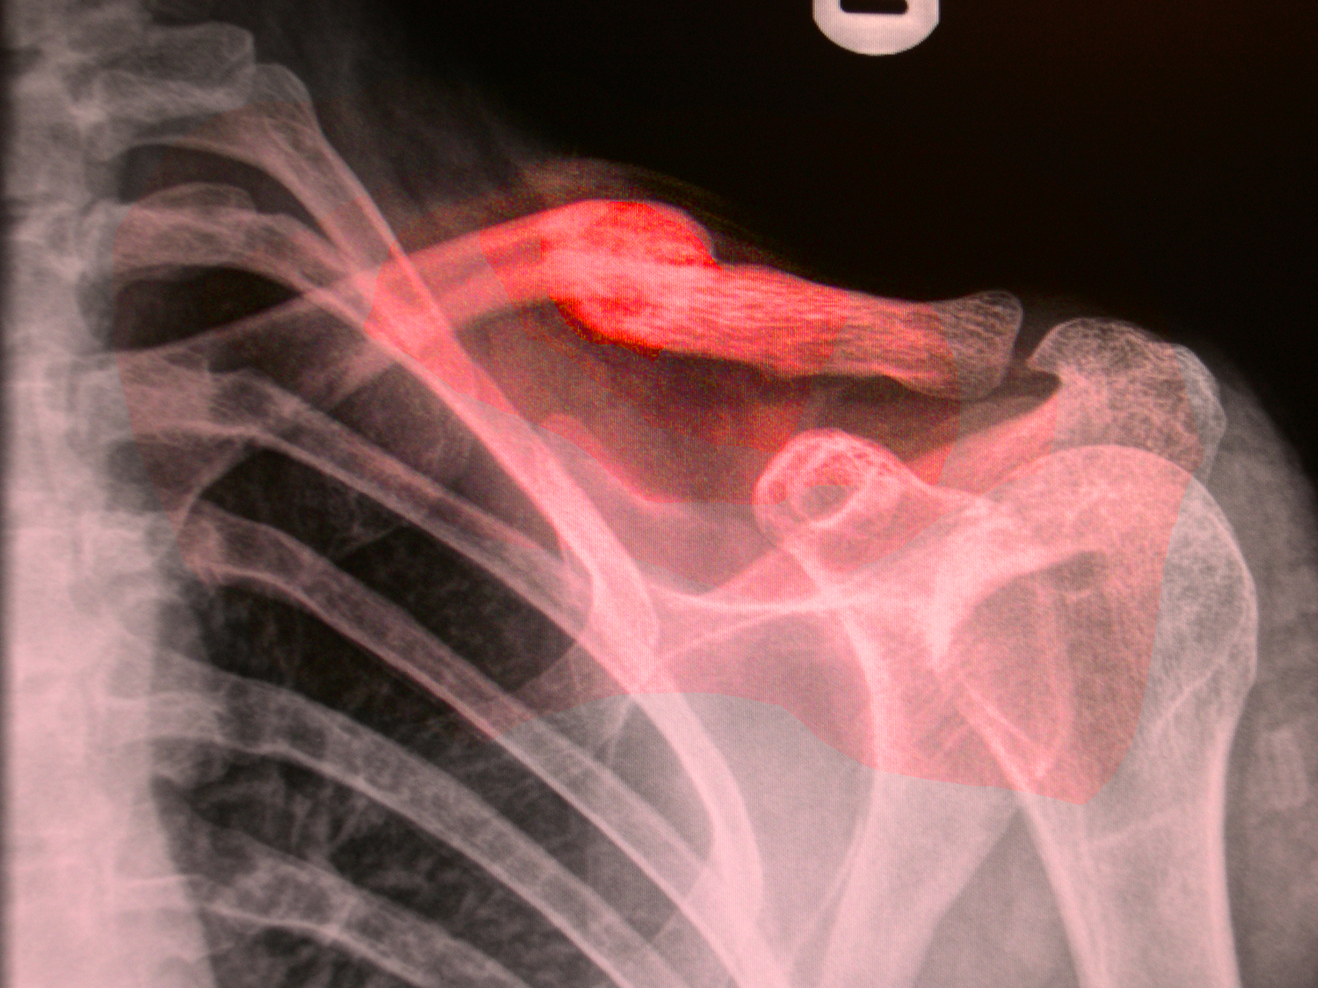

In 'Broken Arm' Henri Michaux observes, ‘A while ago, on the very spot where the accident took place, right after the fracture, when I didn’t know yet that my right elbow was broken, the spirit of my body had silently, secretly deserted it’ (1994: 244). Oliver Sacks describes his broken leg as a ‘phantom’ and ‘a corpse’s leg’ (1990: 88) and that, ‘...it was, in effect, mortified: it was neutrally, functionally and existentially dead’ (1990: 83). Ann Oakley based a book on the experience of breaking her arm and notes that, ‘It’s a shocking to experience part of one’s body as lifeless flesh when one ‘knows’ it isn’t’ (2007: 32). It seems that the lack of functioning and wasting away of a limb could provoke the same sense of abjection as a corpse. Sacks notes that his leg is, ‘...no longer a part of my ‘inner image’ of myself – having been erased from my body image, and also my ego, by some pathology of the most serious and inexplicable kind (1990: 81).

Broken bones, therefore, can present two elements that encourage us to take risks and move beyond everyday routines and restrictions. The first is in wanting to break free from the restricting feelings of being in plaster or having limited in. The second is that alienation to the broken limb moves us to face a state of uncertainty by bringing it forcefully into our awareness.